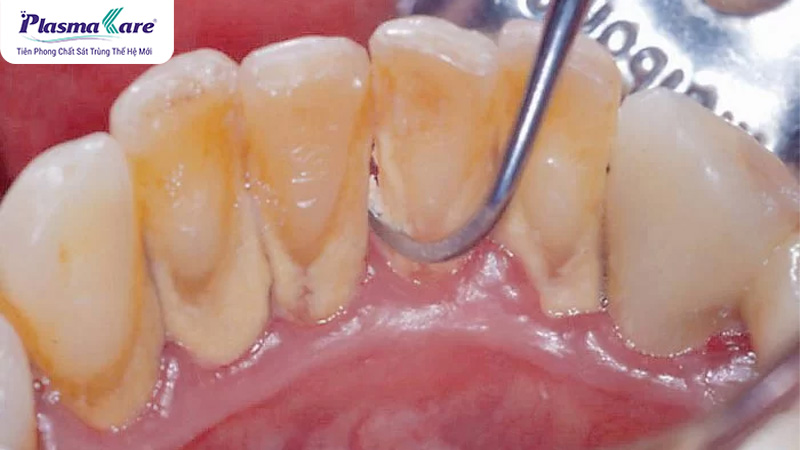

Cao răng là lớp mảng bám cứng hình thành theo thời gian mà nhiều người thường xem nhẹ vì không gây đau nhức tức thì. Tuy nhiên, chính sự tồn tại âm thầm này lại là khởi nguồn của hàng loạt vấn đề răng miệng nghiêm trọng như viêm nướu, viêm lợi, nha chu, tụt lợi và nguy cơ mất răng sớm.

Câu trả lời là CÓ. Lấy cao răng là một thủ thuật nha khoa cần thiết và nên thực hiện định kỳ để bảo vệ sức khỏe răng miệng. Cao răng là mảng bám đã bị khoáng hóa, bám chặt vào bề mặt răng và dưới nướu, không thể loại bỏ hoàn toàn bằng việc đánh răng thông thường. Nếu không được làm sạch kịp thời, cao răng sẽ trở thành ổ vi khuẩn gây viêm nướu, viêm quanh răng và nhiều biến chứng nghiêm trọng khác.

- Ngăn ngừa viêm lợi, viêm quanh răng: Cao răng tích tụ lâu ngày gây kích ứng mô nướu, dẫn đến sưng đỏ, chảy máu chân răng và viêm nhiễm. Việc cạo vôi định kỳ giúp loại bỏ vi khuẩn gây hại, hạn chế nguy cơ tiến triển thành viêm nha chu – nguyên nhân hàng đầu gây tiêu xương và mất răng.

- Bảo vệ chân răng, ngăn ngừa tình trạng răng lung lay: Cao răng bám quanh cổ răng và dưới nướu có thể làm nướu tụt, lộ chân răng và làm giảm độ bám chắc của răng. Lấy cao răng đúng cách giúp duy trì mô quanh răng khỏe mạnh, từ đó hạn chế nguy cơ răng lung lay và rụng sớm.

- Tăng tính thẩm mỹ cho nụ cười: Cao răng thường có màu vàng nâu hoặc đen, khiến răng xỉn màu và kém sạch sẽ. Sau khi lấy cao răng và đánh bóng, bề mặt răng trở nên nhẵn mịn, sáng hơn, giúp nụ cười trông tươi tắn và tự nhiên hơn.